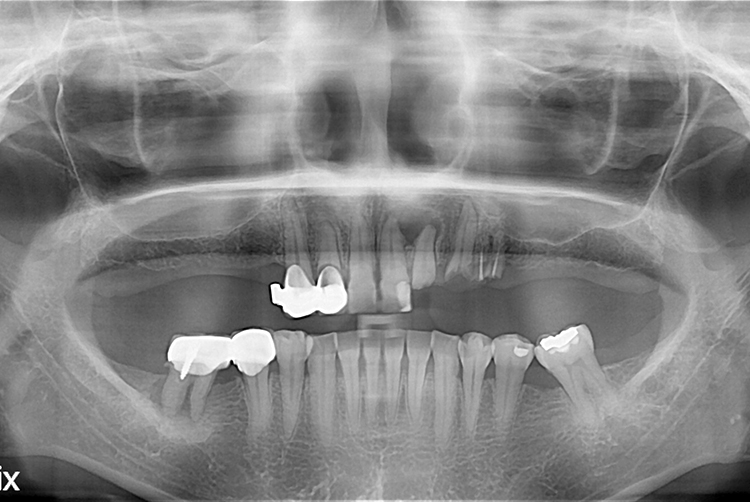

[임플란트] 임플란트

치료전 : 2018-08-22

21.03.17.jpg

치료후 : 2021-03-17

세종치과는 많은 환자와 다양한 케이스를 바탕으로 항상 편안한 임플란트 수술을 제공하고자 노력하고,

오래동안 튼튼히 쓸 수 있는 임플란트 수술을 가장 큰 목표로 삼고 있습니다